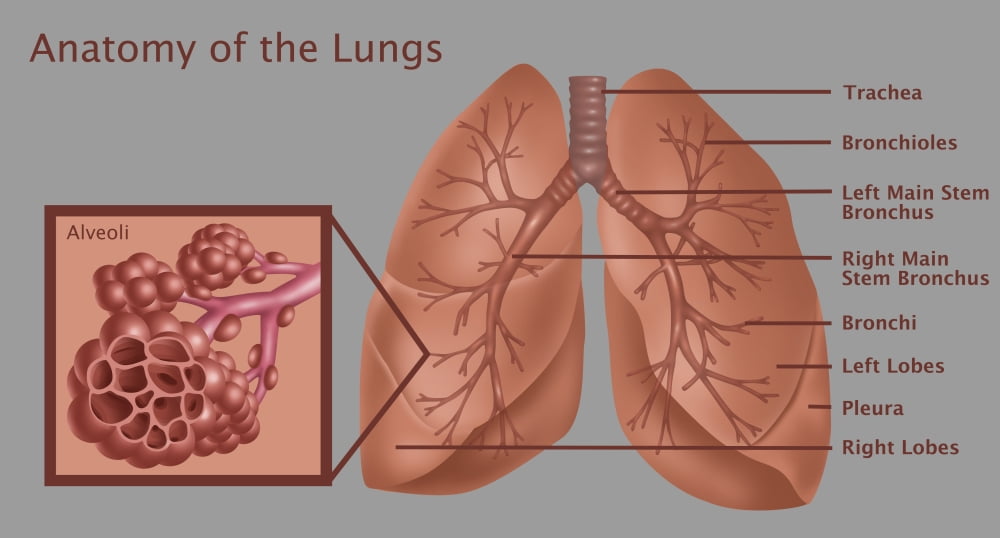

Lung anatomy & function. Alveoli bronchioles anatomy edu adapted. Organs and structures of the respiratory system